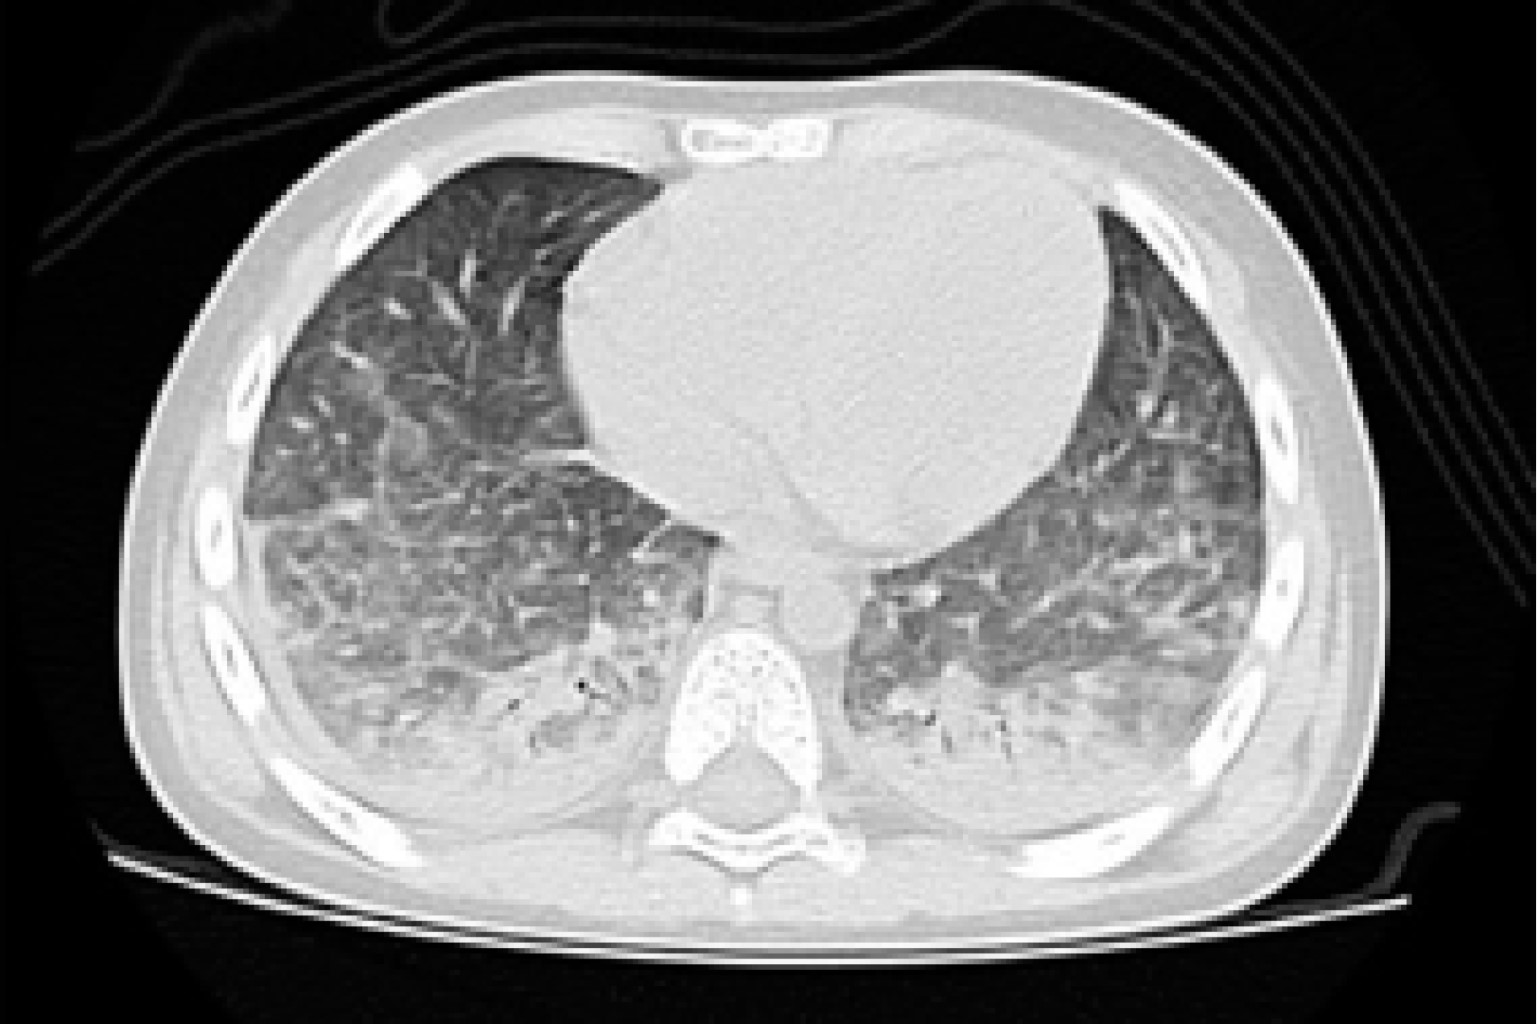

En la radiografía de tórax se muestra un patrón reti?culo-intersticial bilateral difuso, el cual inicia con opacidades centrales, con predominio en lóbulo medio o inferior (Figura 1).2,12-14 La tomografía computarizada de alta resolución es el método de elección radiológico y debe considerarse, incluso si las radiografías de tórax son normales. El hallazgo característico son las opacidades en vidrio despulido bilaterales (Figura 2).2,11,15

Figura 2